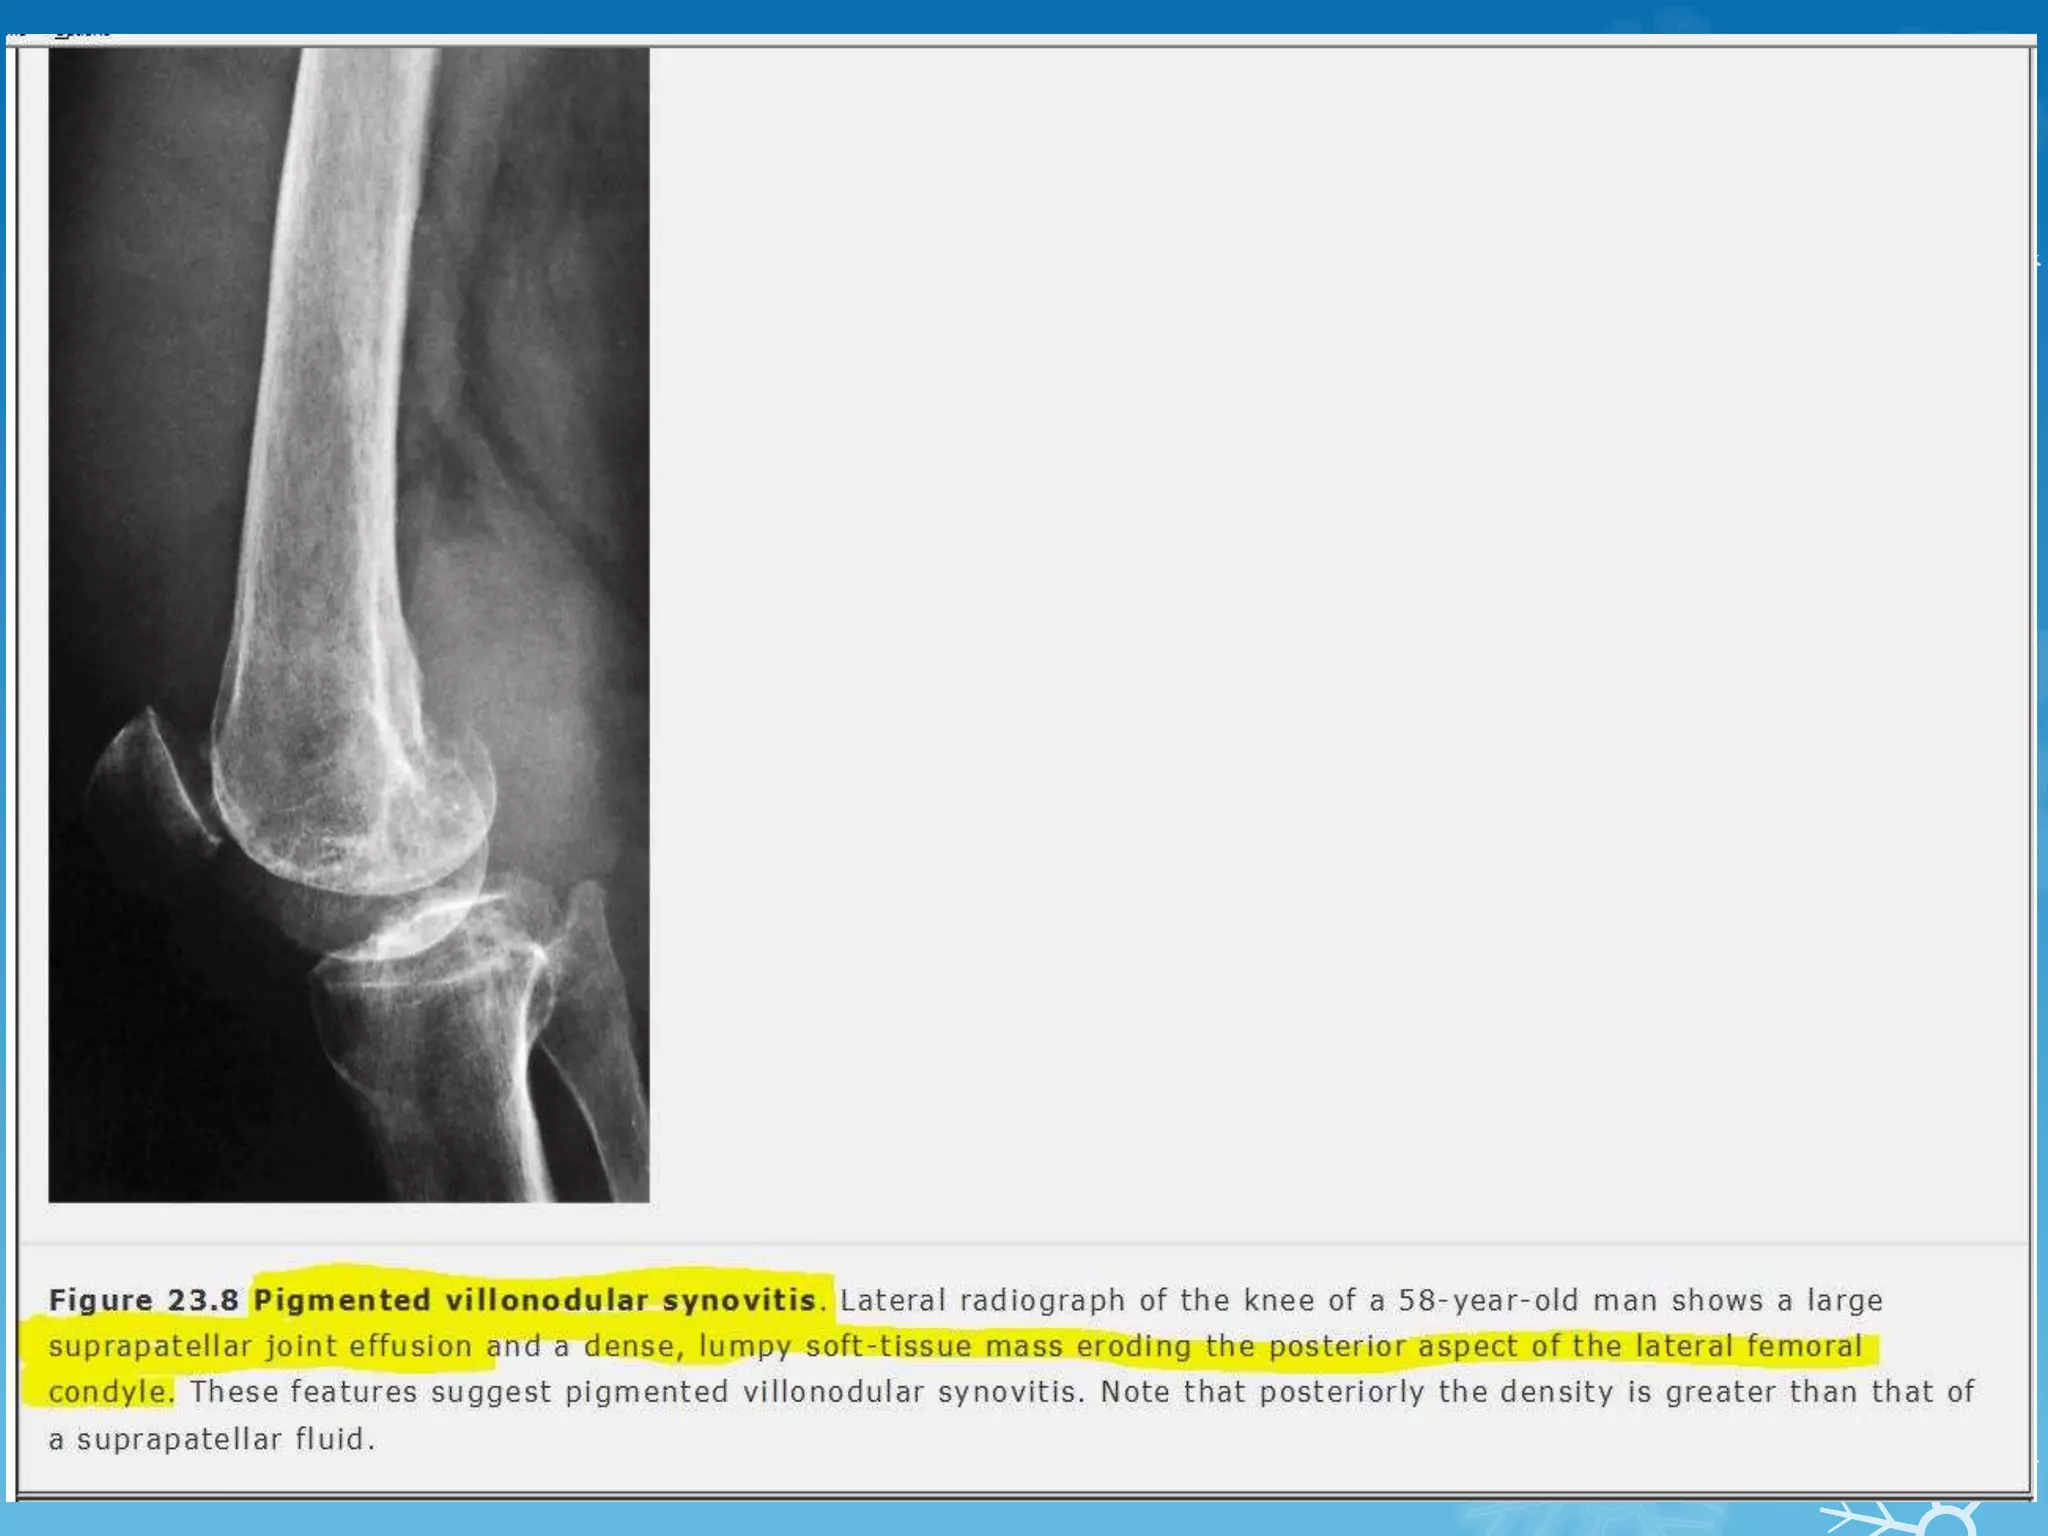

NAME THE SIGN & DIAGNOSIS

Corkscrew sign - midgut volvulus